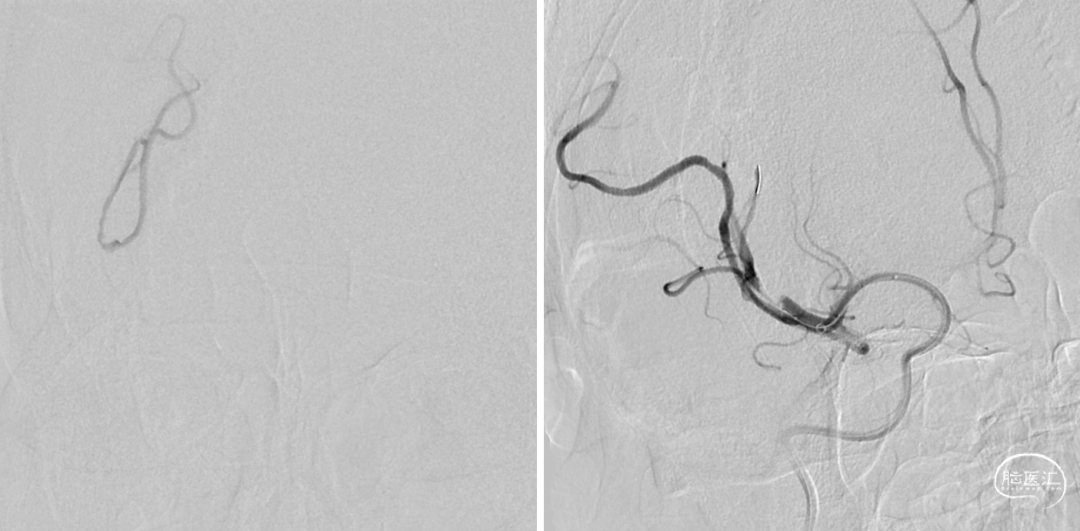

术前CTA提示右侧大脑中动脉M2段闭塞

右侧大脑中动脉上干闭塞(M2),影像评估机械取栓,抽拉结合,M2 位置较远,器械选择关键

headway 17微导管到位

JRecanTM 2.5mm*15mm进入血管远端,小尺寸支架对远端血管损伤小。释放于闭塞段,大网眼设计,充分嵌入血栓

二次取栓

缓慢回收支架并负压抽吸,可见支架显影性良好,同时JRecanTM远端闭合设计有效防止血栓逃逸